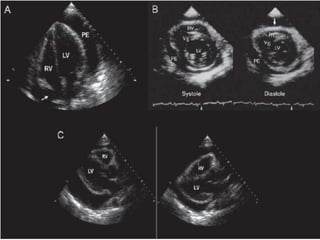

Derrame Pericárdico

Demostrar la presencia

El ecocardiograma es el principal

método diagnóstico

Ecocardiograma

Taponamiento Cardíaco

El signo más característico es el colapso de las cavidades

cardíacas que puede apreciarse por modo M o bidimensional

• Colapso AD

• Colapso diastolico del VD

• Colapso de cavidades izquierdas

• Variaciones recíprocas del diámetro de ambos

ventrículos en relación con el ciclo respiratorio.

• Ingurgitación de la VCI con disminución de las

variaciones respiratorias en su diámetro

• Swinging heart                Inespecífico pero muy sensible

Su ausencia descarta TC

Ecocardiograma 2 D

Ecocardiograma 2D

Ecocardiograma en el

El colapso de las cavidades derechas es el

Indicador más sensible de Taponamiento Cardíaco

Pero las anormalidades del llenado cardíaco

son los indicadores más específicos

Eco Doppler                Alteraciones hemodinámicas

Pulso paradójico